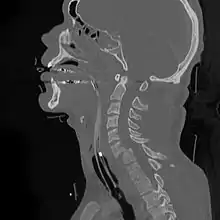

Cervical fracture

A cervical fracture, commonly called a broken neck, is a fracture of any of the seven cervical vertebrae in the neck. Examples of common causes in humans are traffic collisions and diving into shallow water. Abnormal movement of neck bones or pieces of bone can cause a spinal cord injury resulting in loss of sensation, paralysis, or usually instant death.